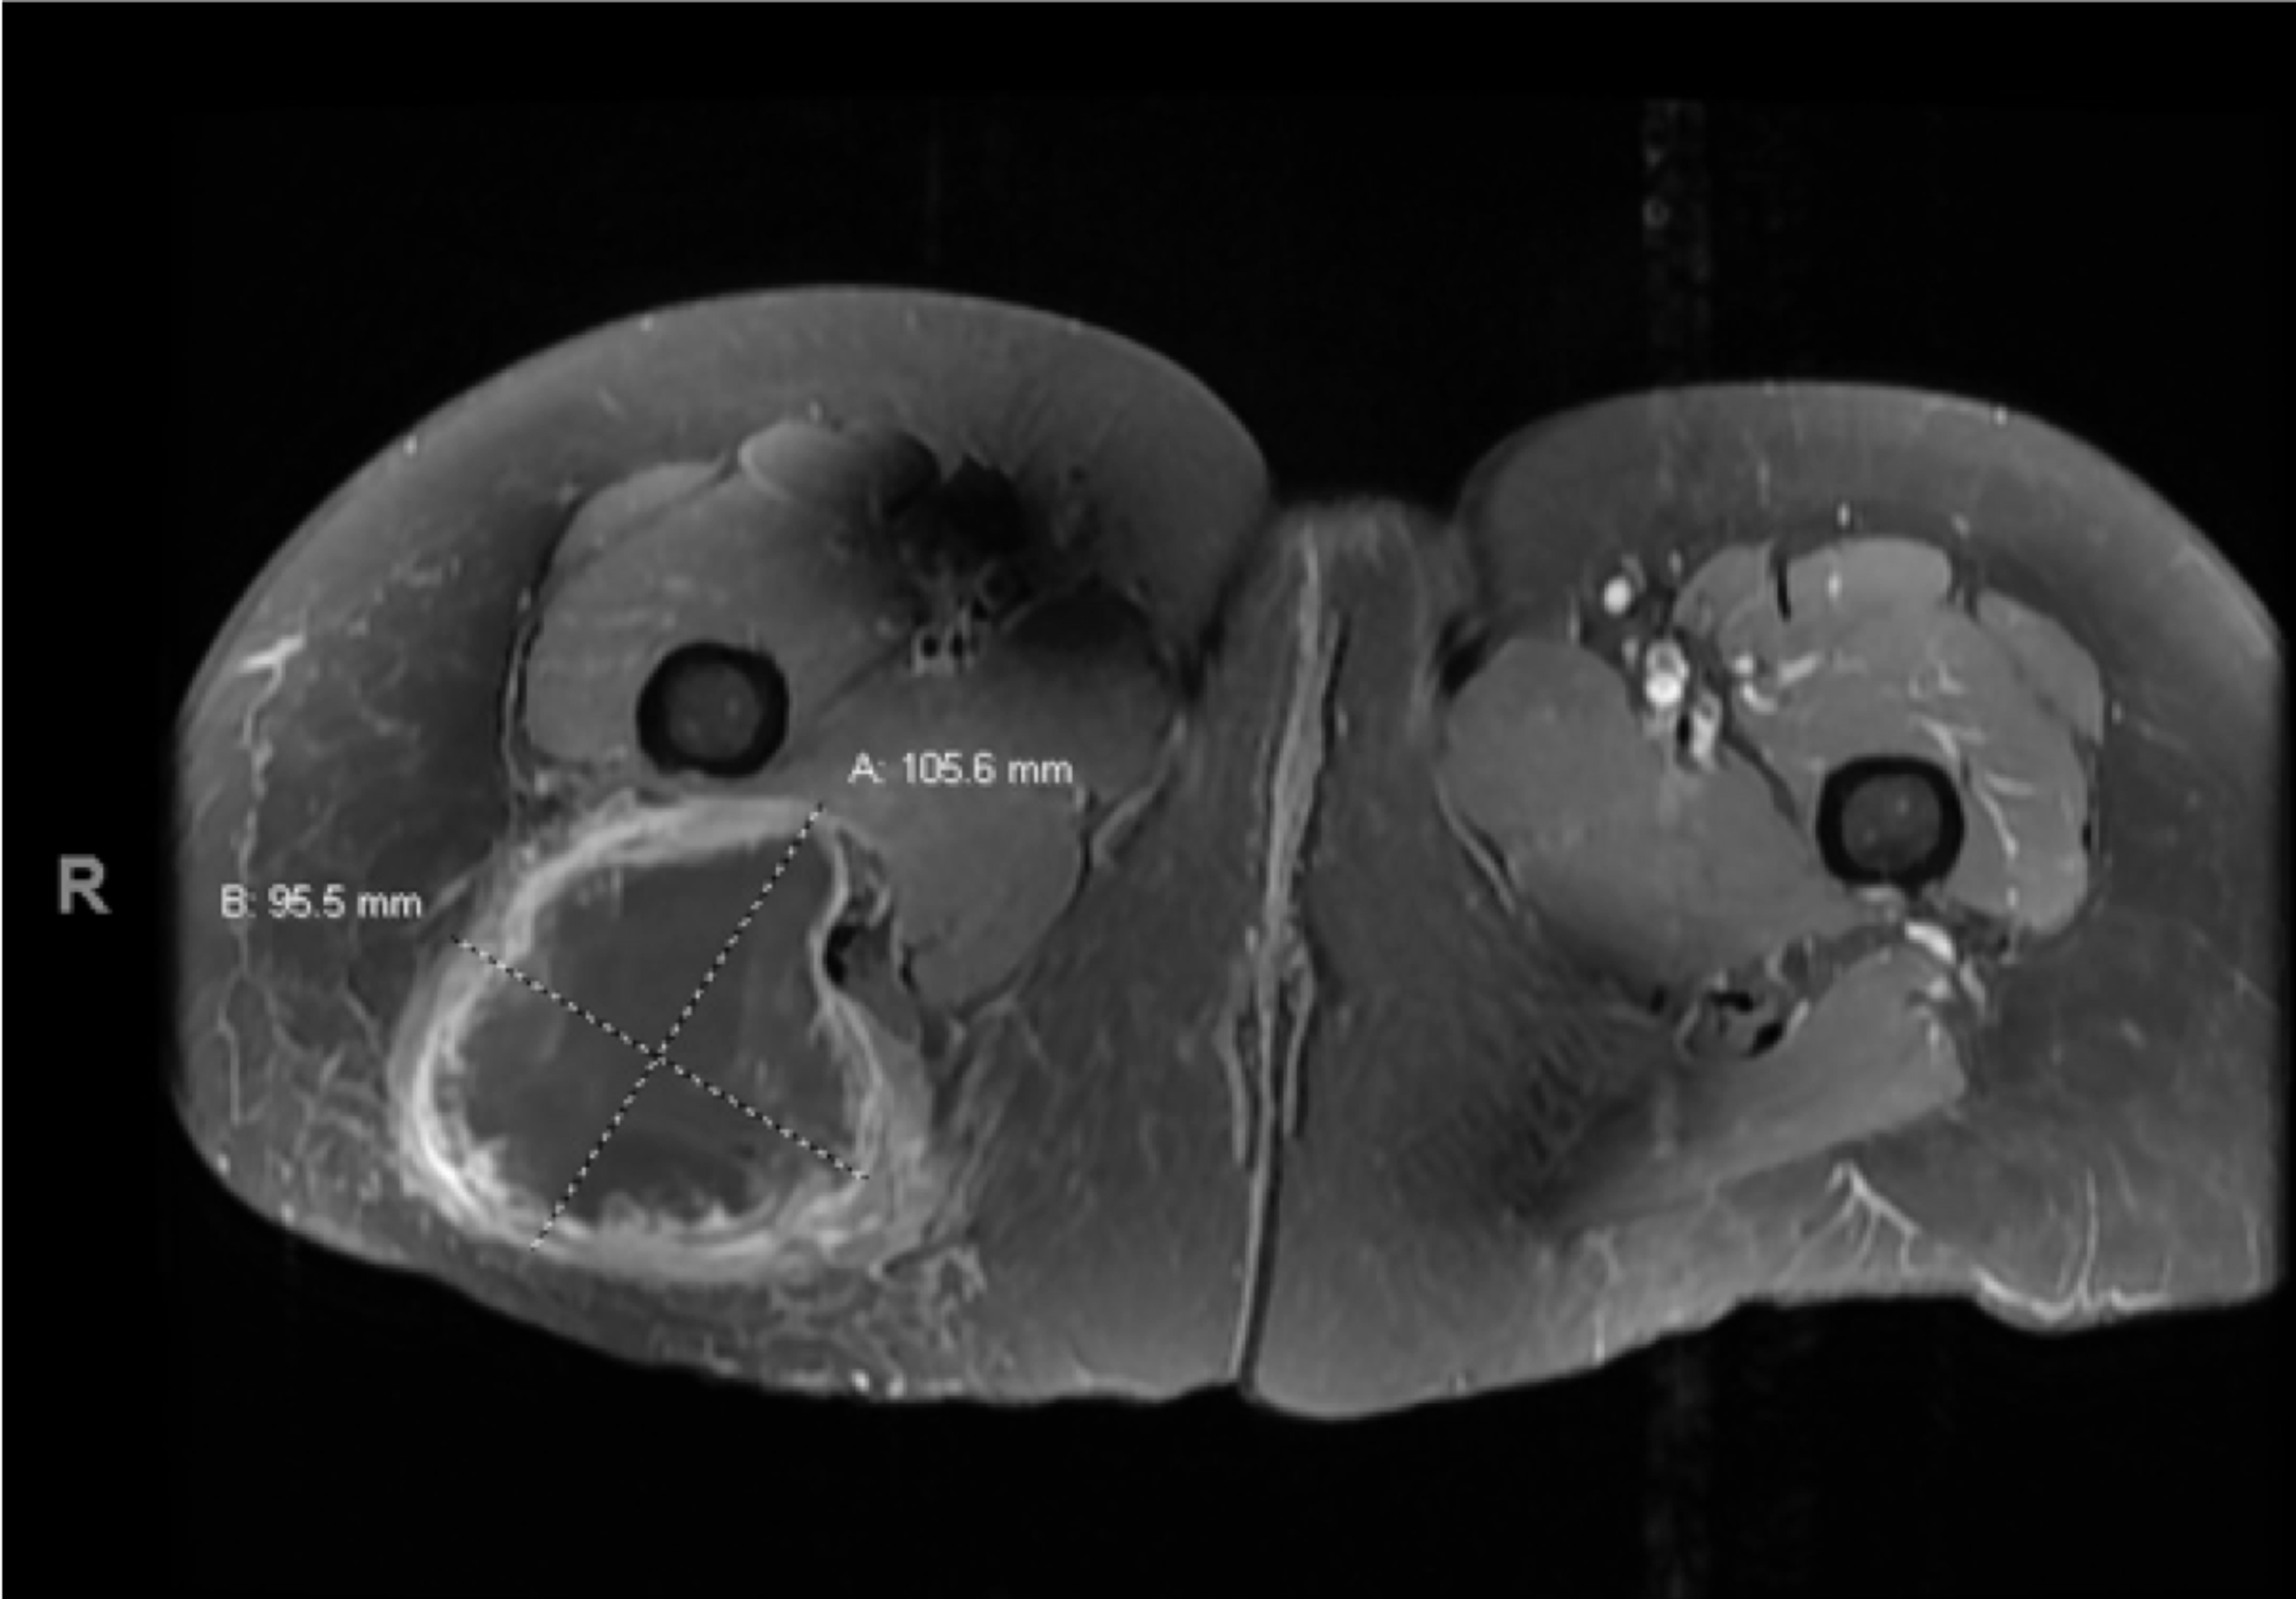

Pain In Left Buttock Cheek Cancer . A number of conditions can cause pain in the buttocks, from minor muscle strains to infections. Most of these conditions aren’t. Several conditions may cause pain in the buttocks, and the likelihood it’s caused by cancer is very low. Soft tissue sarcoma is a rare type of cancer that starts as a growth of cells in the body's soft tissues. Sarcomas can grow anywhere in the body, but they. A sarcoma is a type of cancer that develops in bone or soft tissues like muscle, nerves, fat, fibrous tissues, tendons, or blood vessels. Clinically there was a soft, diffuse, tender mass in the left buttock, with no evidence of abscess or cellulitis.